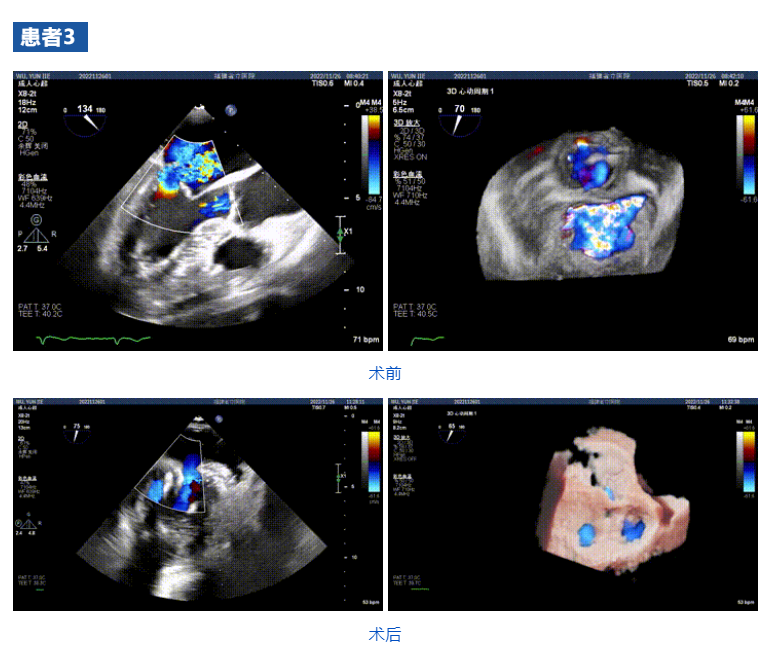

近日,福建省立醫(yī)院心內(nèi)科郭延松教授心臟瓣膜介入治療團(tuán)隊(duì)聯(lián)合浙江大學(xué)醫(yī)學(xué)院附屬第二醫(yī)院王建安教授團(tuán)隊(duì),在福建省首次應(yīng)用JensClip經(jīng)導(dǎo)管瓣膜夾系統(tǒng)為三例二尖瓣重度反流患者開展經(jīng)導(dǎo)管二尖瓣緣對(duì)緣修復(fù)手術(shù)。手術(shù)獲得圓滿成功,患者重獲“心”生。術(shù)后即刻顯示二尖瓣反流顯著改善,術(shù)畢即刻拔管,患者恢復(fù)良好。此次介入手術(shù)的成功再次標(biāo)志著福建省立醫(yī)院心內(nèi)科郭延松教授心臟瓣膜團(tuán)隊(duì)在二尖瓣重度反流修復(fù)介入治療研究領(lǐng)域取得了進(jìn)一步提升,為二尖瓣重度反流患者帶來更多的臨床獲益。

接受治療的三例患者均為器質(zhì)性重度二尖瓣反流(DMR)患者,術(shù)前超聲提示二尖瓣后葉脫垂伴4+反流,左室舒張功能減退。郭延松教授攜同團(tuán)隊(duì)成員陳新敬副教授和洪景宣、方明程、楊清勇主治醫(yī)師、心外科丁杭主任以及超聲科賴寶春、葉振盛主治醫(yī)師共同進(jìn)行病情討論??紤]到患者高齡、基礎(chǔ)疾病多、STS評(píng)分高,為外科手術(shù)極高危患者,不適合進(jìn)行外科開胸二尖瓣手術(shù),因此決定為患者實(shí)施經(jīng)導(dǎo)管緣對(duì)緣修復(fù)介入術(shù)(JensClip經(jīng)導(dǎo)管瓣膜夾系統(tǒng))。

在浙江大學(xué)醫(yī)學(xué)院附屬第二醫(yī)院王建安教授團(tuán)隊(duì)的支持下,手術(shù)經(jīng)股靜脈-房間隔入路,采用全身麻醉插管,在TEE和DSA引導(dǎo)下完成房間隔穿刺。置入JensClip瓣膜夾系統(tǒng)后,在左房調(diào)整瓣膜夾的位置和軸向,后進(jìn)入左室,在TEE引導(dǎo)下捕捉二尖瓣前后瓣葉,并關(guān)閉瓣膜夾。經(jīng)TEE反復(fù)確認(rèn)手術(shù)效果后最終鎖定并釋放瓣膜夾。術(shù)后即刻超聲顯示瓣膜夾位置穩(wěn)定,功能良好,二尖瓣反流由術(shù)前4+減少至微量,手術(shù)圓滿成功。